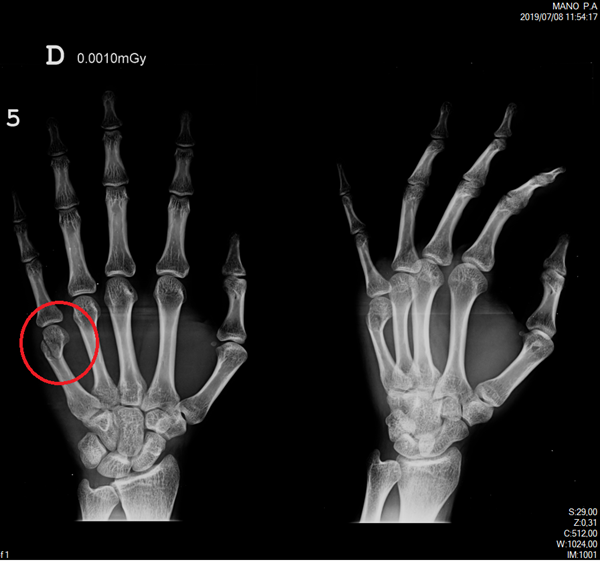

Tengo una rotura del nudillo del quinto dedo de la mano derecha causado por un golpe a una pared. ¿Para la recuperación de esta lesión es 100% necesario la utilización de un yeso? ¿O se podría corregir con una férula? Sufro de ansiedad y el tema del yeso se me torna bastante complicado. Llevo una semana de un total de 3.

Adjunto foto de mi radiografía. De antemano, gracias.